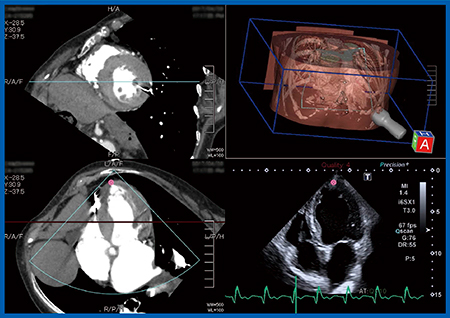

TAVIの実施に当たり,当院では心臓外科医が穿刺する直前に術中エコーにてリアルタイムに心尖部の位置を確認する。しかしながら,本症例は,呼吸機能障害により左肺が過膨張となっており,心尖部が肺の後ろに隠れてしまうため,体位変換が困難な術中には心尖部の描出ができなかった。そこで,Fusion Imagingにて術前のCT画像とリアルタイムの超音波画像を同一画面上に並べて同期表示したところ(図2),心臓外科医も納得し,自信を持って穿刺を行うことができた。

図2 症例:Fusion Imagingによる術前CT画像と術中超音波画像の同期表示